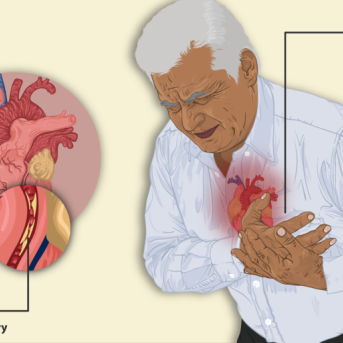

O corpo humano funciona como uma potente máquina. E... Continuar Lendo